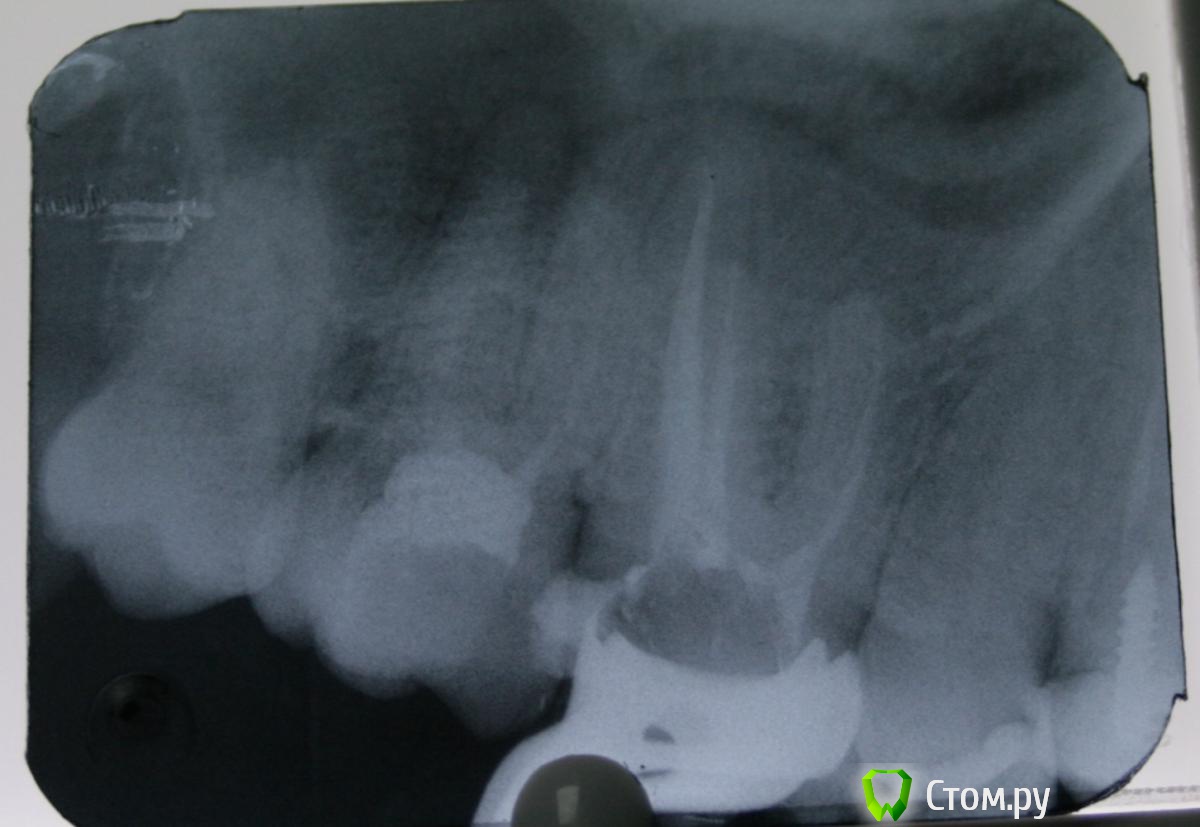

St. Опубликовано 7 ноября, 2014 Автор Поделиться Опубликовано 7 ноября, 2014 Покритикуйте, кому не лень ! Пациентка, в другом учреждении поставили пломбу. Предупредили, что если разболится депульпировать. Разболелся ночью. Попала ко мне по острой боли. Пульпит.Вскрыла - под пломбой чуть мягкого дентина и провалилась в камеру. Ковровая дорожка 10, 15, 20. Мб2 нашла устье, пройти не смогла. Протейперы до Ф1. Хлорка. Кальций. Вр.пломба.Второй визит. Лимонная к-та, гипохлорит. Попыталась ещё пройти мб2 - не смогла. Ещё хлорка, перекись, вода, хлоргексидин. Пломбировка латералкой АН+ и гутта. Апикально мщ -25, дщ - 30.02, небный -35.02.З.ы. смушает средняя треть мщ канала и непройденный мб2.. Ссылка на комментарий

ger_berra Опубликовано 7 ноября, 2014 Поделиться Опубликовано 7 ноября, 2014 Покритикуйте, кому не лень ! Пациентка, в другом учреждении поставили пломбу. Предупредили, что если разболится депульпировать. Разболелся ночью. Попала ко мне по острой боли. Пульпит.Вскрыла - под пломбой чуть мягкого дентина и провалилась в камеру. Ковровая дорожка 10, 15, 20. Мб2 нашла устье, пройти не смогла. Протейперы до Ф1. Хлорка. Кальций. Вр.пломба.Второй визит. Лимонная к-та, гипохлорит. Попыталась ещё пройти мб2 - не смогла. Ещё хлорка, перекись, вода, хлоргексидин. Пломбировка латералкой АН+ и гутта. Апикально мщ -25, дщ - 30.02, небный -35.02.З.ы. смушает средняя треть мщ канала и непройденный мб2.. Не смогли пройти мб2,но нашли,да? С мб2 бывает так,что ход его идет более гризонтально,по сравнению с мб1.Поэтому старайтесь расширить сначала устье,а далее направляйте файл мезиально,как бы к премолярам) ... Файл потихоньку пойдёт) 1 Ссылка на комментарий